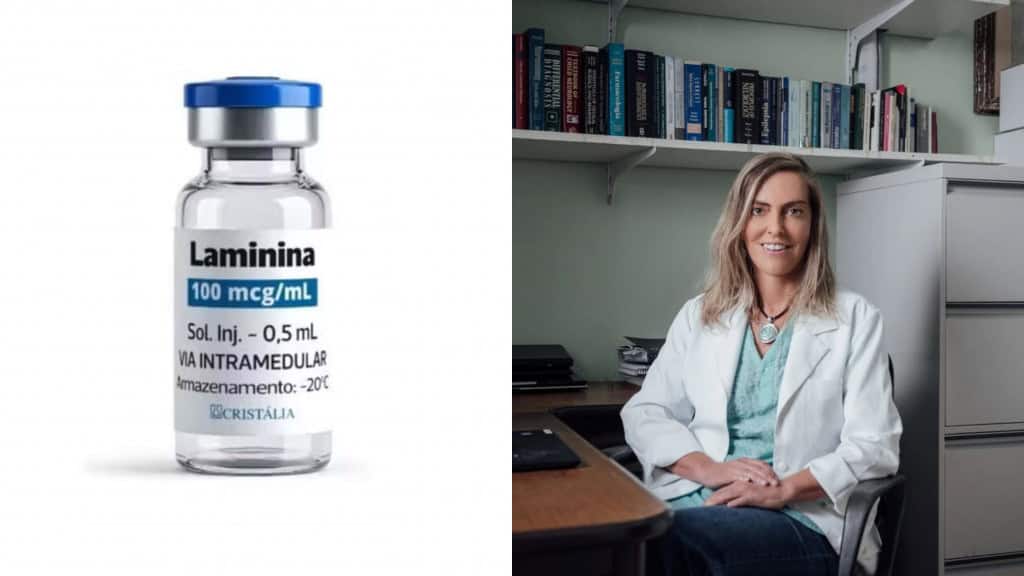

Médicos e pesquisadores que estavam na sessão plenária da American Society of Clinical Oncology (ASCO) se levantaram qua...

Ler maisResultados de pílula para câncer emocionam médicos em congresso de oncologia

Médicos e pesquisadores que estavam na sessão plenária da American Society of Clinical Oncology (ASCO) se levantaram qua...